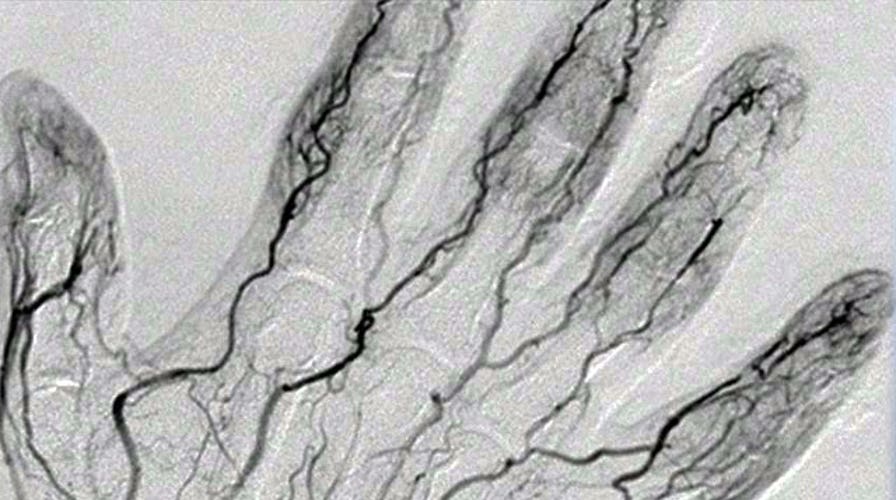

New payment method scans your veins